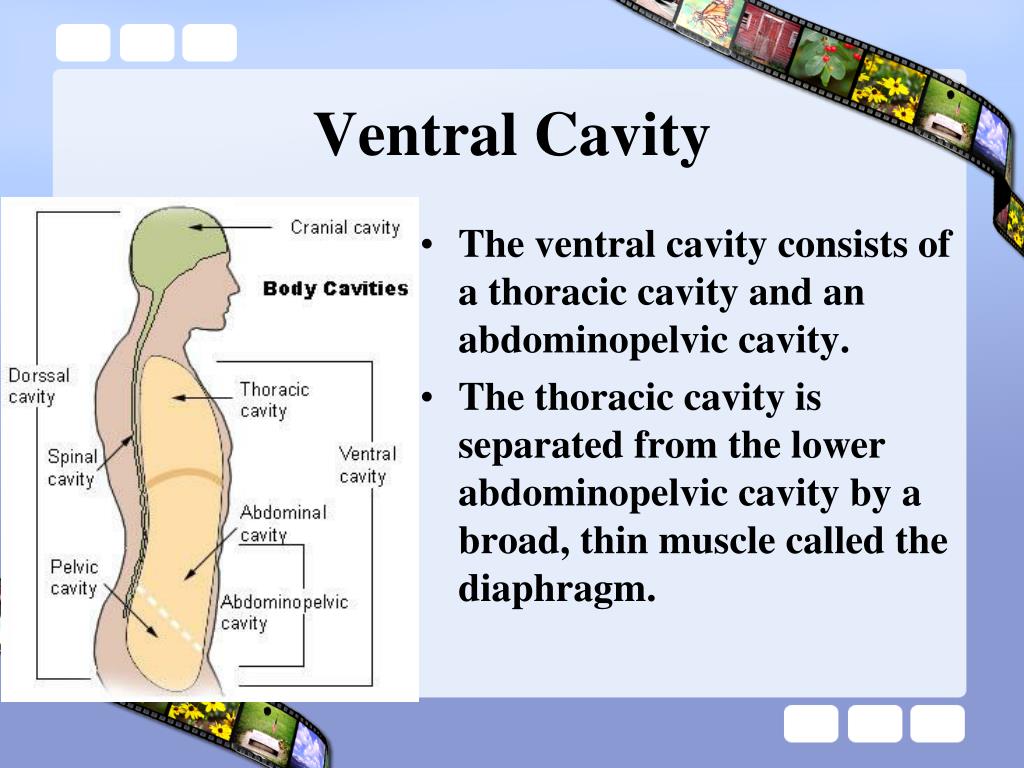

What does the ventntral cavity do?

The ventral cavity, in humans, is actually made up of two separate cavities, separated by the diaphragm, a thin muscle which helps control the expansion and contraction of the lungs. The ventral cavity is sometimes referred to as a coelom, or true body cavity.

What muscle that subdivides the ventral body cavity?

contains urinary bladder, reproductive organs, and rectum name the muscle that subdivides the ventral body cavity diaphragm which organ system would not be represented in any of the body cavities

The ventral cavity is subdivided into the thoracic and abdominopelvic cavities. The thoracic cavity is further divided into the pleural and pericardial cavities, while the abdominopelvic cavity is further divided into the abdominal and pelvic cavities.

The ventral cavity is subdivided into the thoracic and abdominopelvic cavities. The thoracic cavity fills the chest and is subdivided into two pleural cavities and the pericardial cavity. The pleural cavities hold the lungs, and the pericardial cavity holds the heart.

two separate cavitiesThe ventral cavity, in humans, is actually made up of two separate cavities, separated by the diaphragm, a thin muscle which helps control the expansion and contraction of the lungs. The ventral cavity is sometimes referred to as a coelom, or true body cavity.